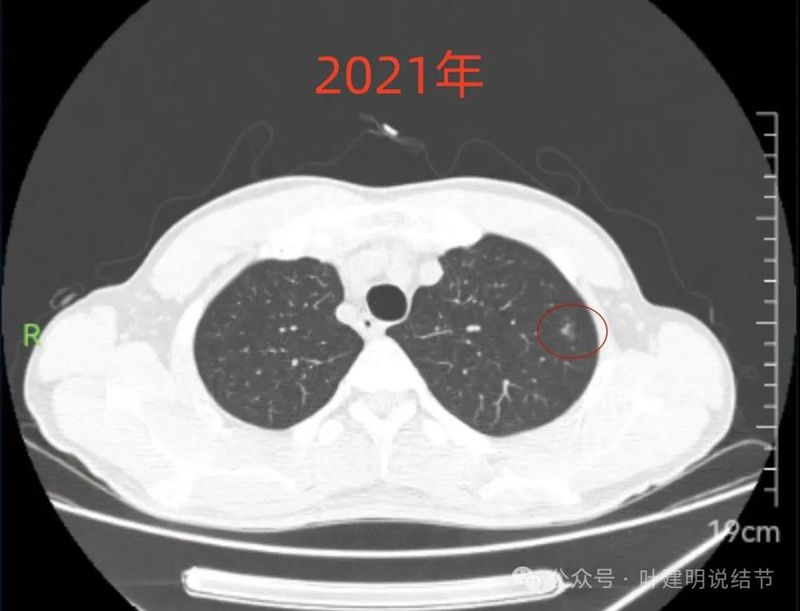

病灶上缘即偏实性,非圆形或类圆形。

边上有少许淡面模糊的磨玻璃成分。

轮廓欠清,瘤肺边界也不清晰。

病灶出现,偏实性密度。

整体密度较高,且轮廓欠清。

感觉膨胀性不够。